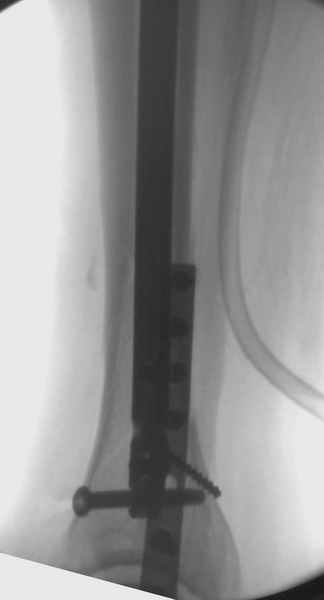

Здесь мы использовали новый Synthes Nail с дополнительными дырками, в проксимальной части 4: по две косых и поперечные (один стандартный а другой динамический), в дистальной части две поперечные, прямая и косая. Вес больного более 120 кг, нагрузку начнем через месяц.

Получилось красиво, поздравляю. Вверху можно было ограничиться одним винтом во фронтальное статическое отверстие, зачем два 45-градусных?

При такий спирали задний край tibia может быть сломан - нет ли этого в данном случае? На всякий случай можно было ввести 1-2 винта 4,5 мм спереди назад мимо гвоздя. Хотя самый дистальный блокирующий винт, возможно, зацепил этот отломок. А какой тут диаметр гвоздя и locking винтов?